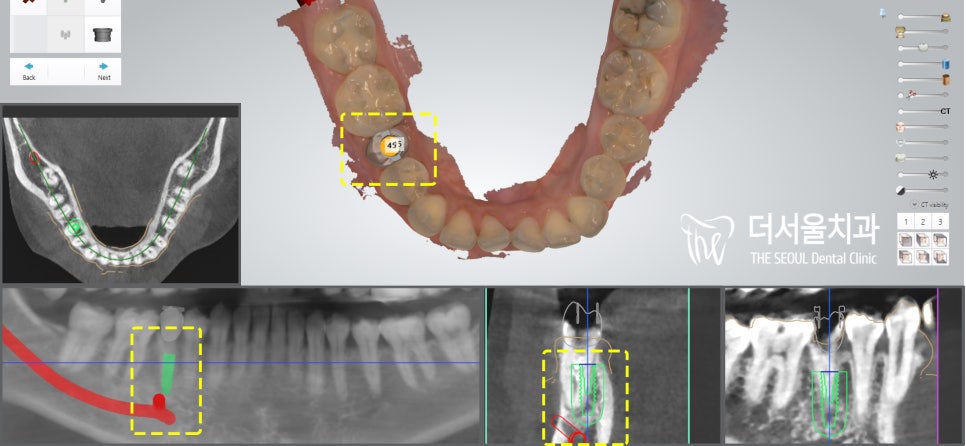

3. 디지털 임플란트

다만 엑스레이를 통해

살펴보았을 때

긍정적인 부분도 있었는데요,

부러진 치관을 제외하고

아직은 잇몸뼈의 상태가 양호했고,

염증도 없어서

발치 즉시 수술이 가능한 케이스였습니다.

네비게이션과 비슷한 개념으로

컴퓨터 프로그램을 통해

미리 모의 시술을 할 수 있어

픽스처의 적절한 식립 각도,

위치, 방향, 깊이까지

사전에 계획할 수 있습니다.